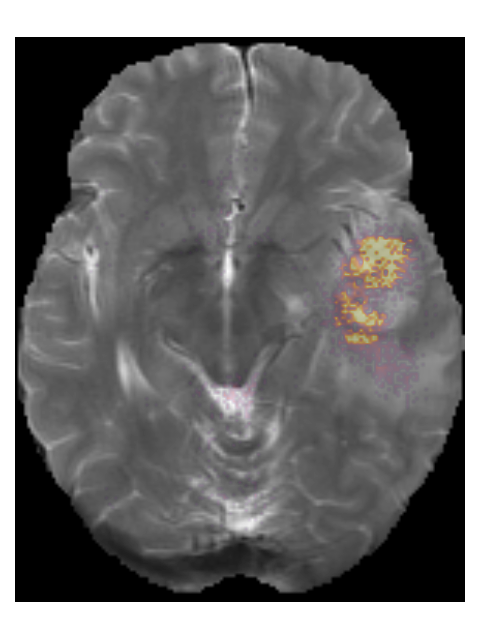

To provide insight into the behavior of our model we created saliency maps, which show which parts of the scans contributed the most to the prediction. These saliency maps are shown in Figure 6 for two example patients from the test set. It can be seen that for the LGG the network focused on a bright rim in the T2w-FLAIR scan, whereas for the HGG it focused on the enhancement in the post-contrast T1w scan. To aid further interpretation, we provide visualizations of selected filter outputs in the network in Appendix D, which also show that the network focuses on the tumor, and these filters seem to recognize specific imaging features such as the contrast enhancement and T2w-FLAIR brightness.

To demonstrate the automatic segmentations made by our method, we randomly selected five patients from both the TCGA-LGG and the TCGA-GBM dataset. The scans and segmentations of the five patients from the TCGA-LGG dataset and the TCGA-GBM dataset are shown in Figures 12 and 14, respectively. The DICE score, Hausdorff distance, and volumetric similarity coefficient for these patients are given in Table 7. The method seems to mostly focus on the hyperintensities of the T2w-FLAIR scan. Despite the registrations issues that can be seen for the T2w scan in Figure 14(d) the tumor was still properly segmented, demonstrating the robustness of our method.